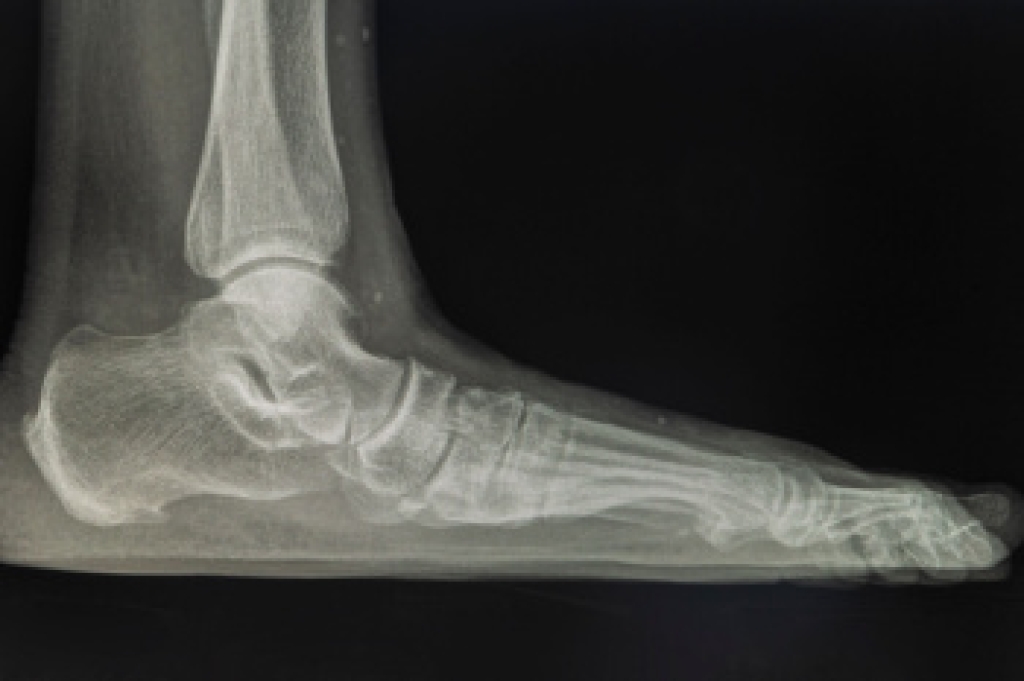

Juvenile idiopathic arthritis, or JIA, is a type of arthritis that affects children and adolescents. The exact cause is unknown, but it is believed to result from a combination of genetic and environmental factors that trigger an autoimmune response. In JIA, the immune system mistakenly attacks the joints, causing inflammation and pain. The condition can affect one or multiple joints, often leading to swelling, stiffness, and limited movement. Common symptoms include joint pain, especially in the morning, fever, and fatigue. Some children may also experience growth problems and eye inflammation. JIA can be classified into different types based on the number of joints affected and other features. If your child’s feet are affected by any of the above symptoms, it is suggested that you consult a podiatrist who can provide the necessary care for relief.